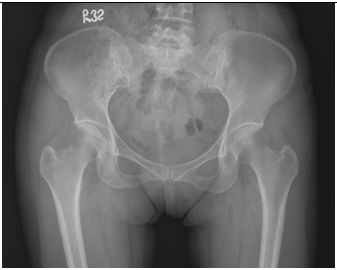

7. 一位47歲的女性患者5年前曾有一次虹彩炎(Iritis)發生,及有一段時期早上起床時會有下背疼痛,後來便逐漸好轉。最近8個月來頸部及兩側肩關節經常酸痛而求診。檢查結果顯示ANA(-),RF(-),CRP 1.74,HLA-B27(+)。另外,家族史中顯示父親有亦有類似情況,而弟弟為乾癬患者。本患者的骨盆的X光照相如圖 ,請問這位患者的最可能的診斷為何? (A) Rheumatoid arthritis (B) Undifferentiated spondyloarthropathy (C) Systemic lupus erythematosus (D) Osteoarthritis (E) Ankylosing spondylitis